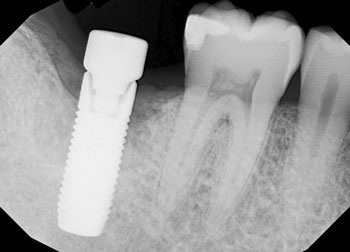

The following radiographs demonstrate representative surgical cases treated with a laser-assisted protocol, illustrating resolution of peri-implant radiolucency, stabilization of crestal bone levels and improved bone density patterns over time.

Fig. 1 illustrates tooth #29, restored with a dental implant placed 18 years prior, which presented with vertical osseous defects on both the mesial and distal aspects. Follow-up radiographic evaluation demonstrates adequate osseous fill on the mesial and distal aspects following therapy.

Fig. 1: Initial and follow-up radiographs of dental implant at site #29.